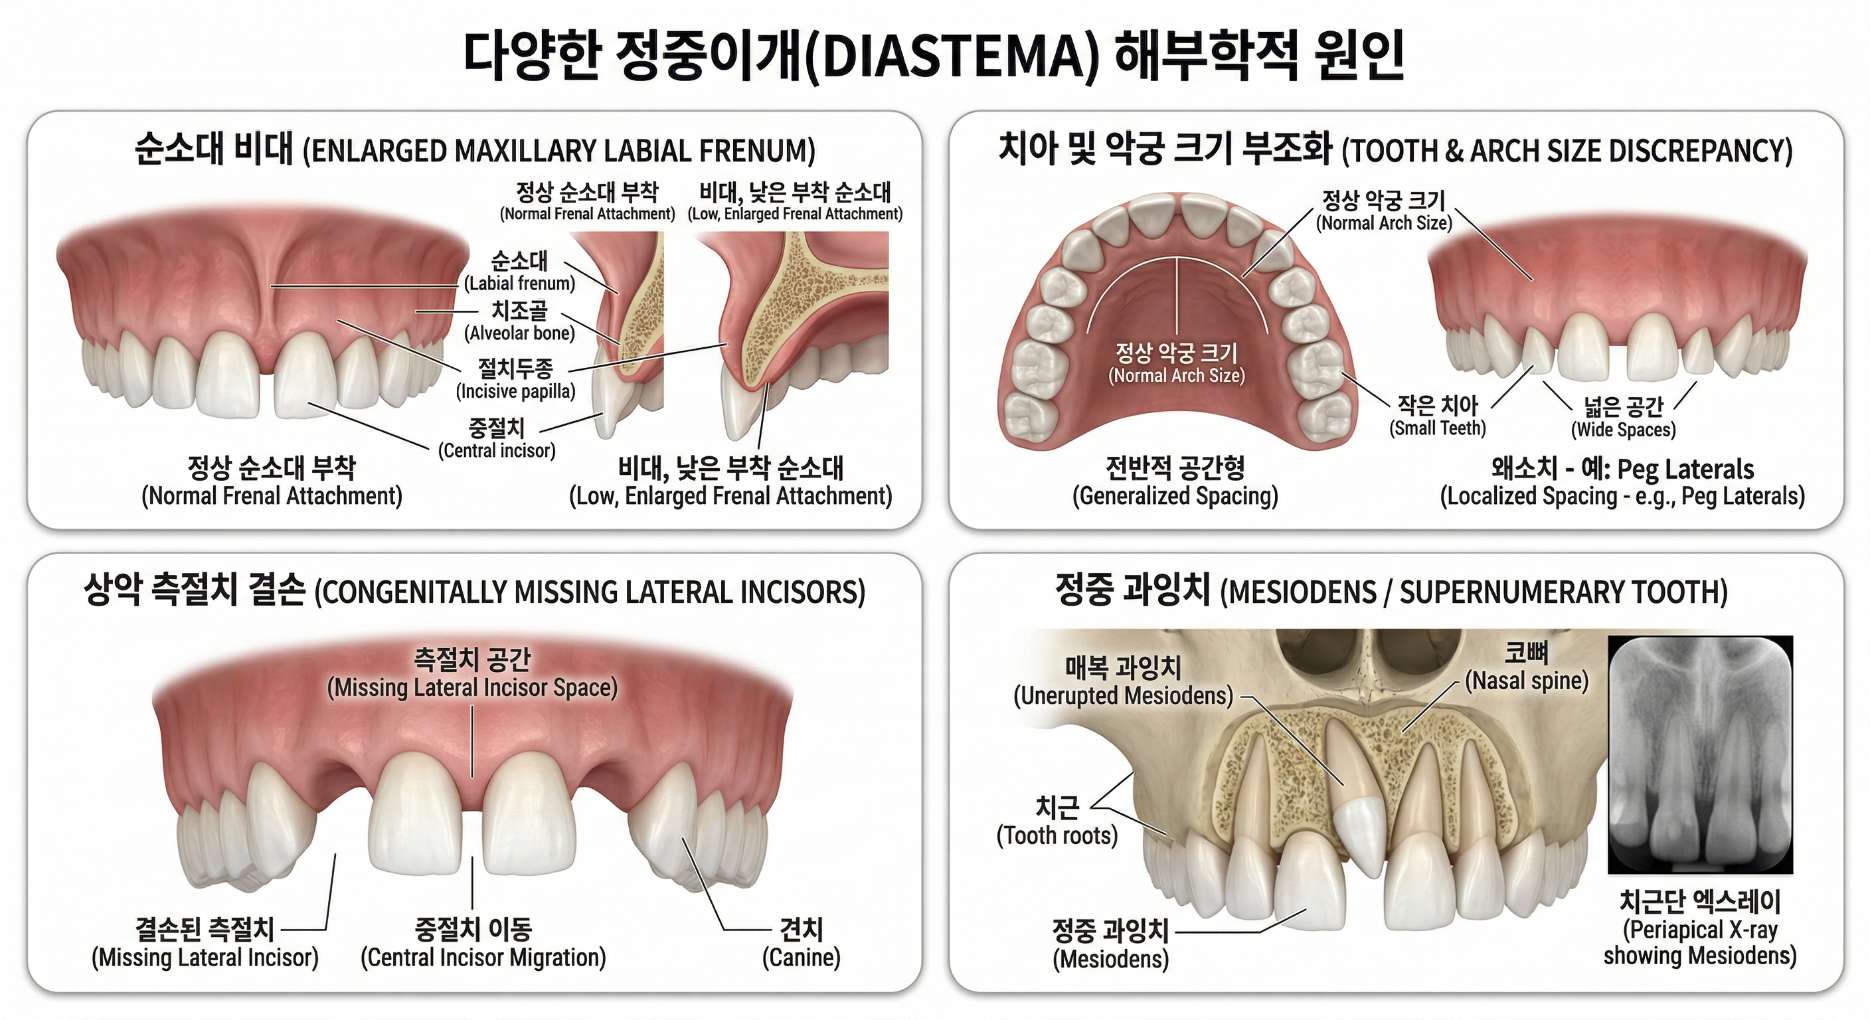

앞니 사이가 벌어지는 현상인 정중이개(Diastema)는 다양한 원인에 의해 발생합니다.

선천적으로 턱뼈의 크기에 비해 치아가 너무 작거나 치아 개수가 부족한 경우 발생할 수 있으며, 윗입술과 잇몸을 연결하는 순소대(입술 주름띠)가 치아 사이로 너무 깊게 내려와 붙어있는 경우에도 틈이 벌어질 수 있습니다.

또한 손가락을 빨거나 혀를 내미는 등의 후천적인 습관, 혹은 잇몸 질환으로 인해 치아를 잡아주는 잇몸뼈가 약해지면서 치아가 부채꼴로 뻗어나가 틈새가 생기기도 합니다.